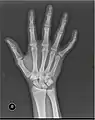

صورة بالأشعة السينية لليد اليمنى. رأس الزند هو العظم الطويل ، أسفل يمين الصورة. الزائدة الإبرية للزند تظهر ناتئة في نهاية العظم.